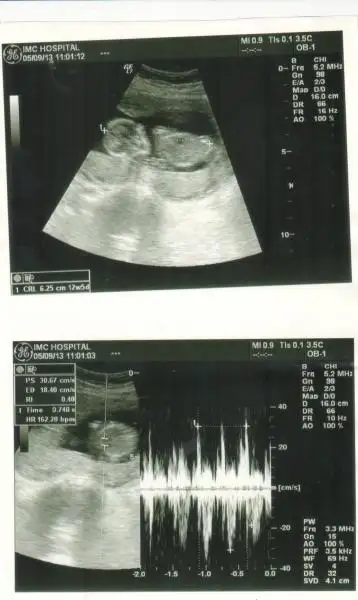

resim 1

Eki Görüntüle 473828 gordugunuz gibi ust taraftaki simgedende anlasildigi gibi eger cikinti paralel ise kiz

yok 30°lik bir aciyla yukari dogru bakiyorsa %99 oglunuz olacak demektir simdi bi kac ornek resimler daha koyacagim kiziminkide dahil